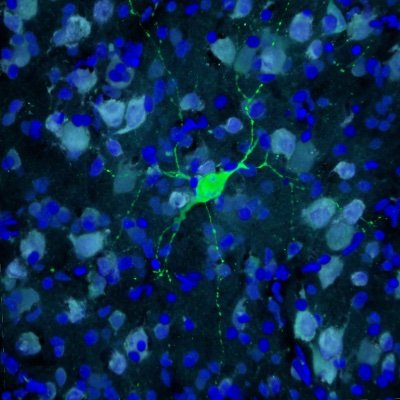

Happy to announce the publication of our latest paper in BSaF providing open-source probabilistic atlases for the ventral BNST, dorsal BNST and paraventricular hypothalamus derived from 7T manual segmentations! https://t.co/yuhPuhtzzL